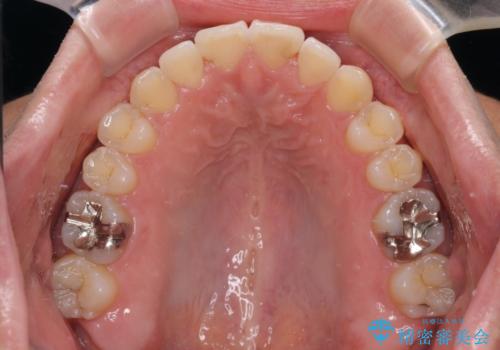

開咬とデコボコを整える インビザライン矯正治療

- 前歯の開咬と叢生を気にして来院された患者様です。

開咬の治療は、前歯を閉じるように動かすとともに、上下臼歯を圧下(骨内にめり込ませる)させることで進めて行きます。

インビザラインは臼歯の圧下を効果的に行えるため、インビザラインを用いて矯正治療を行うこととしました。また、アンカースクリューを用いて、口元の突出感の改善を図りました。

オープンバイトは舌の突出癖により誘発され、治療後も突出癖が残っている容易に後戻りしてしまいます。

治療期間を短縮するためにも、舌突出癖の改善が極めて重要となります。